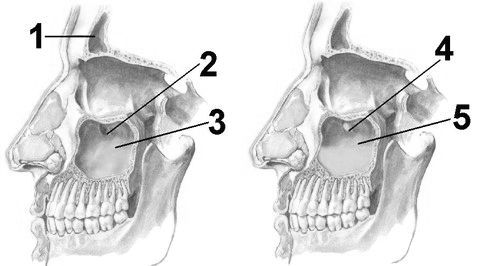

Зліва - норма. 1 - лобова пазуха, 2 - сполучення верхньощелепної (гайморової) пазухи, 3 - вільна порожнину верхньощелепної пазухи.

Праворуч - гайморит. 4 - сполучення перекрито гноєм і не пропускає повітря, 5 - в пазусі скупчився гній.